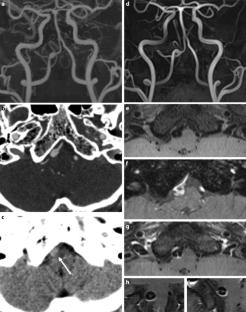

The HR-MRI findings were classified into complete normalization (normal lumen and wall with or without mild enhancement, n = 6), complete normalization with minimal wall changes (focal wall thickening with enhancement but normal luminal angiography, n = 8), incomplete normalization (focal wall thickening with enhancement with dilatation and stenosis on luminal angiography, n = 4), dissecting aneurysm (fusiform aneurysm with residual dissection findings, n = 8) and occlusion (small outer arterial diameter with diffuse contrast enhancement, n = 3).

The use of HR-MRI can demonstrate the distinguishing morphological features of chronic stage of spontaneous and unruptured ICAD as complete normalization, complete normalization with minimal wall changes, incomplete normalization, dissecting aneurysm and occlusion.